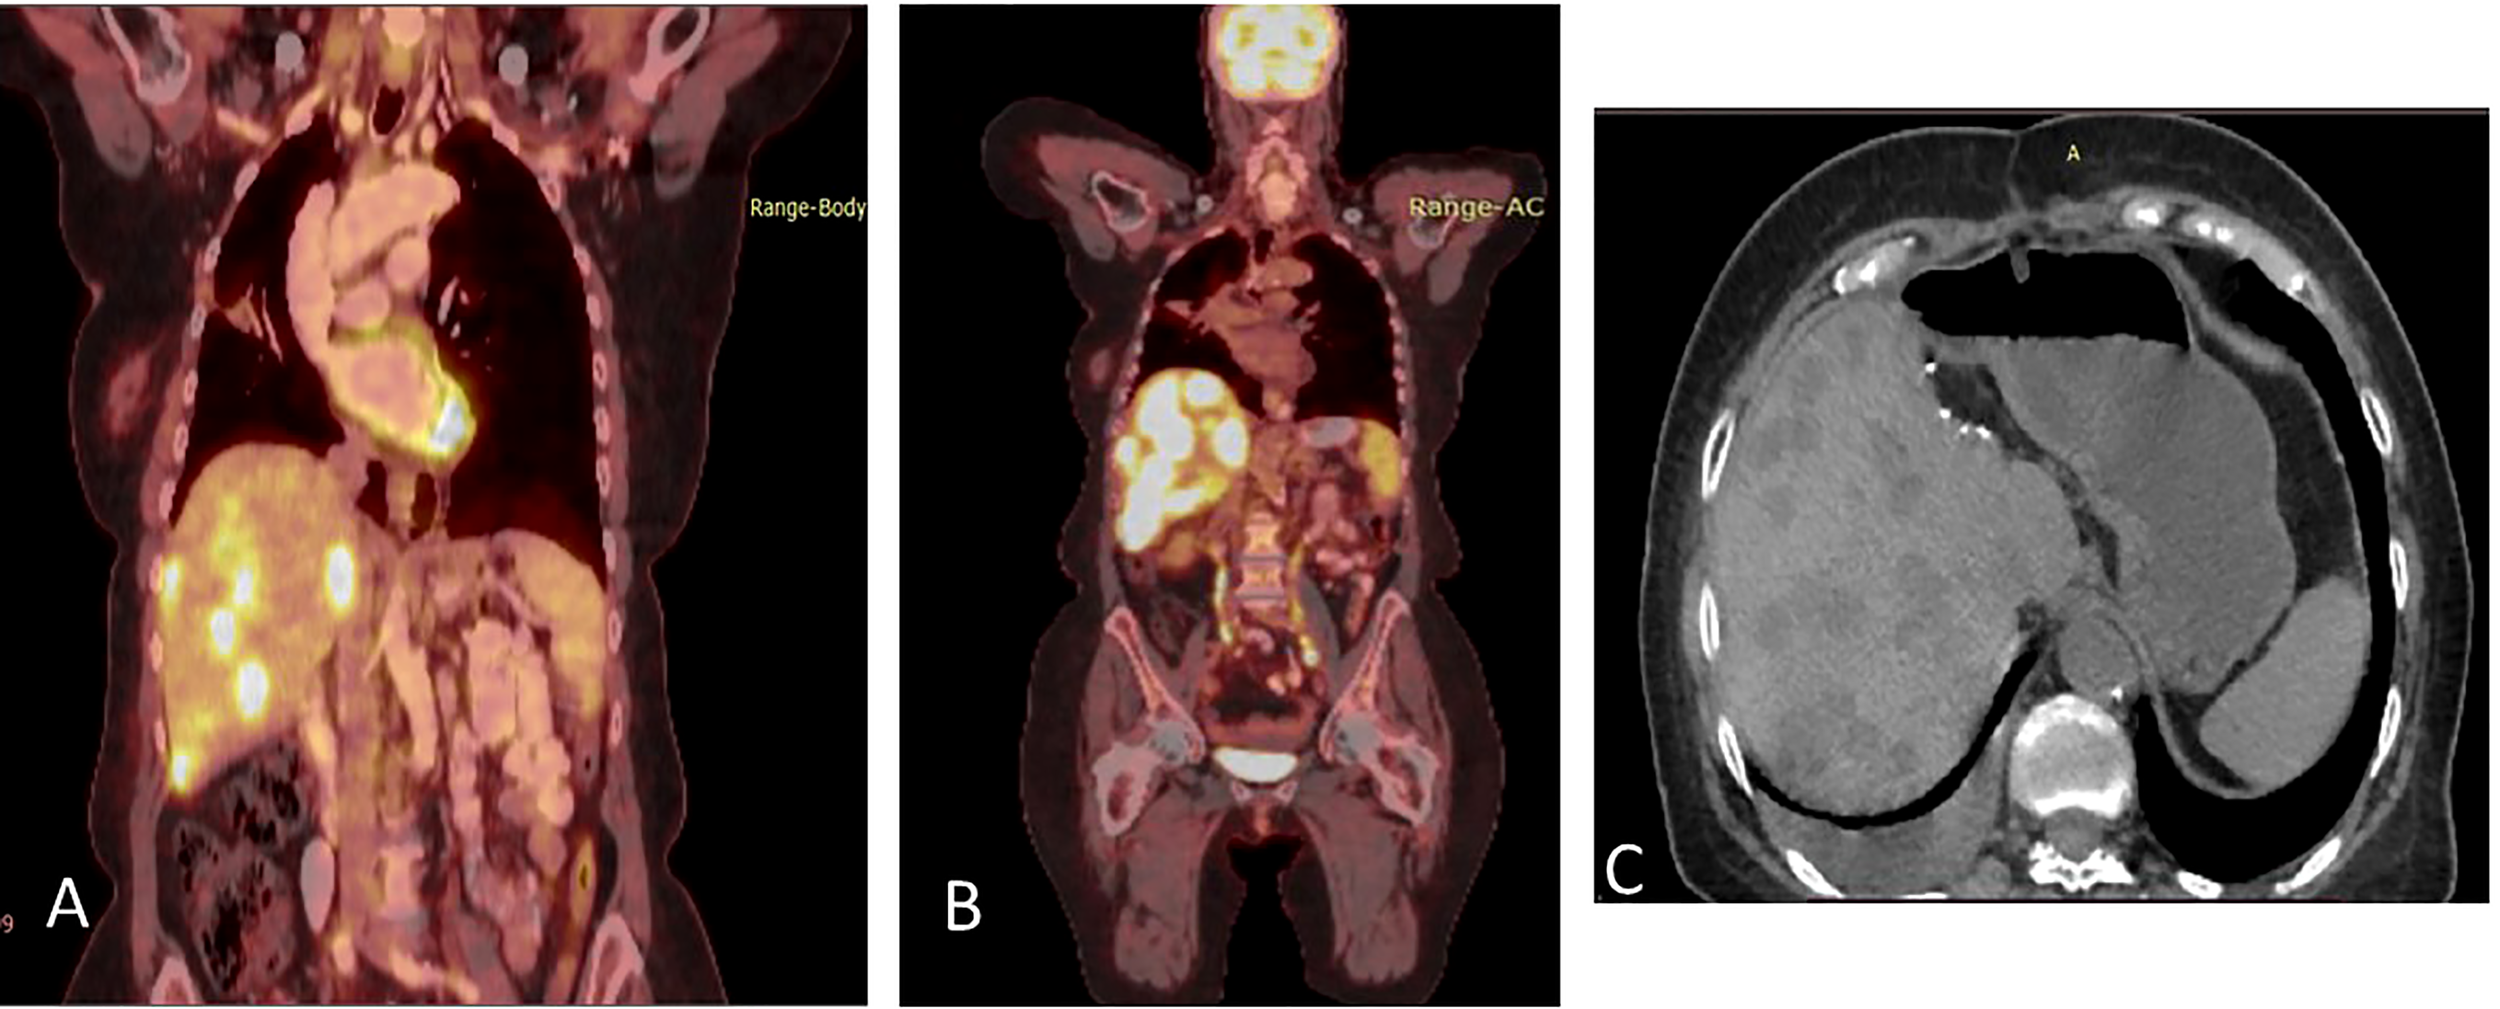

Disease progression in the right pleura was identified in November 2019 with a right-sided pleural effusion. Osimertinib was initiated, demonstrating a partial response (Figures 5A, B).

Figure 5

(A) Coronal PET-CT scan from November 2019 shows a pleural effusion and lesions with increased uptake of FDG-18, indicating disease progression. (B) Three months later, following Osimertinib demonstrated partial response. (C) February 2021, showing a new pleural lesion indicating disease progression on Osimertinib.

Upon mild local disease progression In February 2021, a lung biopsy, and a comprehensive genomic test (Tempus) were performed. Tissue biopsy demonstrated a poorly differentiated cancerous lesion with 50% Ki67 (neuroendocrine marker). At the same time a liquid biopsy resulted: EGFR exon 19 deletion (41%), EGFR T790M (11.9%), and a MKRN1-BRAF fusion gene, as shown in Table 2. In follow-up, the patient’s disease progression was mostly stable containing small nodules in the lungs (Figure 5C).

Osimertinib alone was continued until June 2021, at which time there was further disease progression into the pleura, liver, peritoneum, and bones (Figure 6A). To combat this, the patient underwent 3 cycles of carboplatin and pemetrexed, alongside Osimertinib with further disease progression (Figure 6B).

Figure 6

(A) Coronal PET-CT scan, from June 2021, showing new multiple lung and liver lesions with increased uptake of FDG-18, indicating further disease progression on osimertinib. (B) Two months later, August 2021, they demonstrated massive disease progression with lung, liver, and bone metastases following chemotherapy plus Osimertinib. (C) Three months later, November 2021, showed significantly decreased uptake of FDG-18, indicating partial response following adding dabrafenib plus trametinib to Osimertinib.

In August 2021, osimertinib was initiated alongside BRAF kinase inhibitor trametinib and dabrafenib, to combat the MKRN1-BRAF fusion gene acting as a mechanism of resistance. This resulted in clinical and RECIST partial response (Figure 6C). In February 2022, the patient passed away due to lung disease progression.